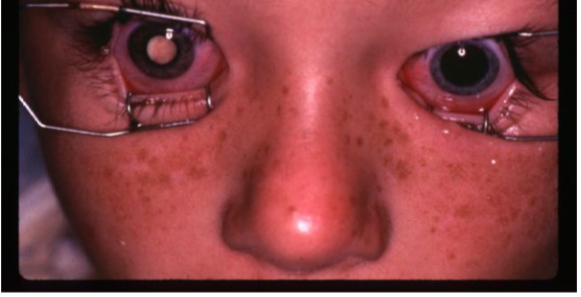

retinoblastoma

ocular manifestations:

leukocoria

strabismus

dome-shaped lesion

whitish pink nodular mass

can cause RRD

secondary glaucoma & pseudouveitis

iris neo

retinoblastoma

retinoblastoma

retinoblastoma